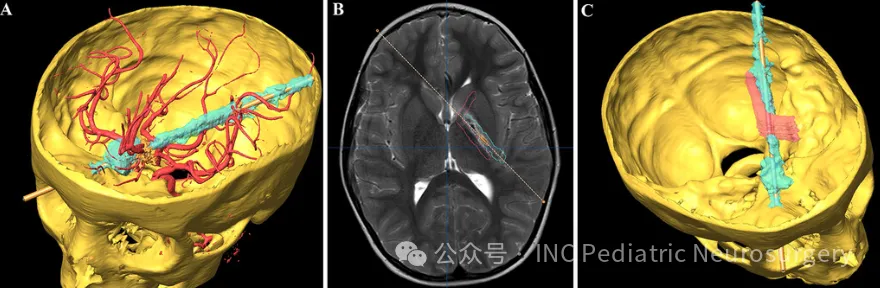

▼下图为患者头骨及损伤轨迹的三维(3D)重建

▼下图为尖端通过右侧眼眶进入颅骨的轨迹(A)及其与脑实质内功能结构的解剖关系(B)